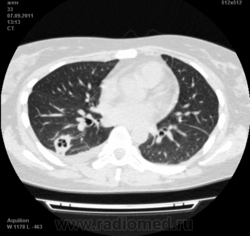

Пациентка Ж.1977 года рождения.

Дебют системного заболевания в 1988 году, когда впервые появились боли в мелких суставах кистей, скованность, лихорадка, похудение. При обследовании установлен диагноз РА.В настоящее время постоянно принимает метипред 8 мг/сут. Наследственность отягощена: у родного брата системное заболевание соединительной ткани, у матери ревмотоидный артрит, у родной тети по линии отца - СКВ.

На фоне адекватной  п/воспалительной   проводимой терапии: положительной динамики клинически нет. Сохраняется непродуктивный кашель,  лихорадка до 38 гр. Цельсия.

Могут ли изменения в легких быть проявлением РА???